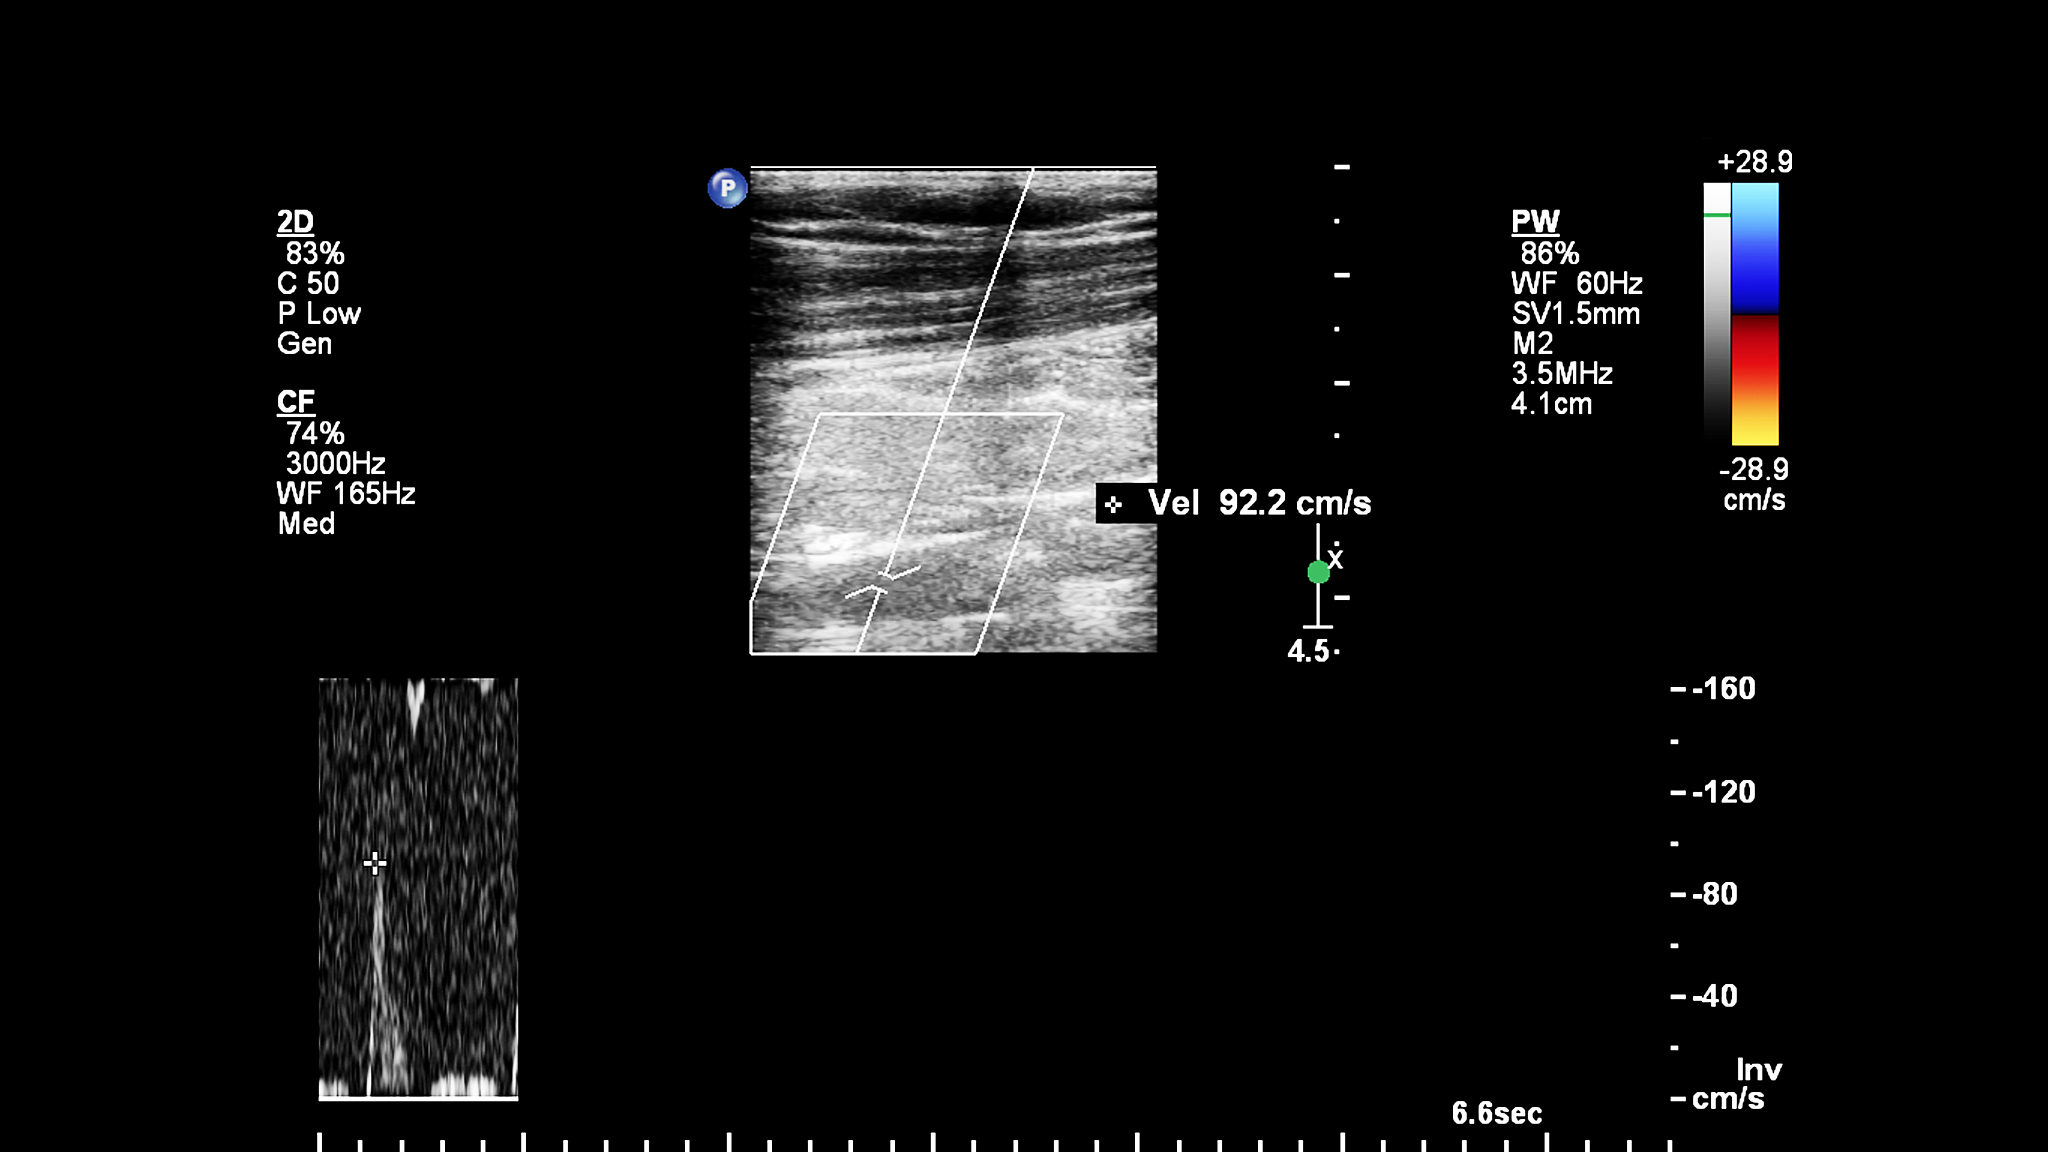

血管内超声诊断导管探头显影的趋势是越来越普遍和广泛应用。随着医疗技术的不断发展,血管内超声诊断导管探头显影已经成为一种非常有效的诊断工具,可以帮助医生更准确地诊断和治疗疾病。此外,随着血管内超声诊断技术的不断改进和完善,导管探头显影的精度和可靠性也得到了显著提高,使得这种诊断方法更加受到医生和患者的信任和欢迎。总体来说,血管内超声诊断导管探头显影的趋势是不断向着更加精准、安全、便捷和高效的方向发展。

血管内超声诊断导管探头显影趋势:更精准、安全、便捷